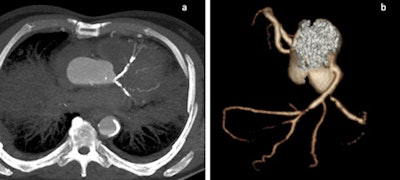

The quality of postmortem angiography using the technique of multiphase PMCTA is high. The vessels of the thorax (a) and abdomen (b) are visible in a volume-rendered 3D reconstruction. All images courtesy of Dr. Silke Grabherr, PhD.An international working group, the Technical Working Group Post-mortem Angiography Methods (TWGPAM), was created in February 2012 to develop systematic and target-oriented research. It now consists of nine participating centers from six European countries: Switzerland (University of Lausanne and University of Basel), Germany (University of Hamburg, University of Munich, and University of Leipzig), the U.K. (University of Leicester), Italy (University of Foggia), Poland (University of Krakow), and France (University of Toulouse).